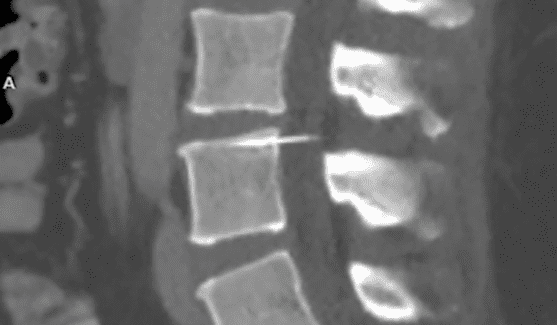

I medici le hanno detto che si trattava di qualcosa alla schiena, ma nel 2017, dopo una tac  ha scoperto che il suo dolore cronico era causato da un piccolo pezzo di ago che si era rotto durante l’epidurale e si era alloggiato nella sua spina dorsale dal 2003.

L’ago è lungo 3 cm. e si trova conficcato per 3/4 dentro un osso della sua spina dorsale.

In una normale epidurale un ago viene inserito nella spina dorsale per iniettare l’anestetico. Nel caso di Amy il medico ha incastrato l’ago attraverso il canale spinale e nella spina dorsale.